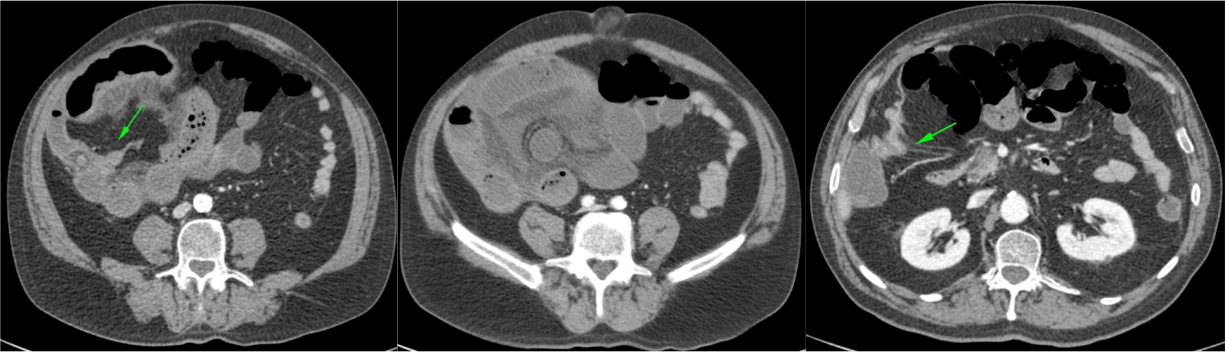

Normalmente se forman en el estómago de pacientes con historia personal previa de cirugía gástrica o enfermedad psiquiátrica. Los bezoares pueden darse en el estómago, intestino delgado o intestino grueso y pueden presentarse aislados y ser múltiples.

Pacientes jóvenes entre 15 – 19 años. Pueden asociar enfermedad psiquiátrica o antecedes de cirugía gástrica. Síntomas: indigestión/malestar estomacal, dolor, náuseas, vómitos, diarrea, anorexia, pérdida de peso, úlceras gástricas, obstrucción intestinal

- CT abdominal: Es la prueba de elección.

- Masa con baja densidad intraluminal + patrón de burbujas de aire moteado ( patrón característico).

- Edema de pared y engrosamiento de mucosa.

- Obstrucción intestinal: cambios de calibre y dilatación de asas pre estenosis. El CT puede determinar la causa, localización y grado de obstrucción intstinal.

- Sd de Rapunzel: cola de pelo que se extiende desde el estómago al intestino y puede producir obstrucción.

- Perforación: líquido libre y neumoperitoneo.

- El CT puede ayudar a distinguir entre un bezoar y particulas de comida. Los bezoares son redondos u ovoides, flotan en la superficie de agua/aire rodeados del contenido gástrico y que además muestran menor densidad que las partículas de comida. Los bezoares grandes tienden a rellenar todo el lumen y muestran burbujas distribuidas en el intersticio de la masa. Sin embargo, en ocasiones puede ser dificil difrenciar un bezoar de un cantidad considerable de comida retenida o de las heces si se localizan en el colon. Un hallazgo que puede ayudarnos, es identificar que dicha masa esta produciendo una obstrucción.

- La ventana estándar abdominal de (level, 40 H; width, 350 H) puede hacer muy dificil el diagnóstico de bezoar. Es recomendable bajar el Nivel/Level de la ventana hasta los L -1oo H o jugar con dichos niveles hasta identificar mejor las características del bezoar.